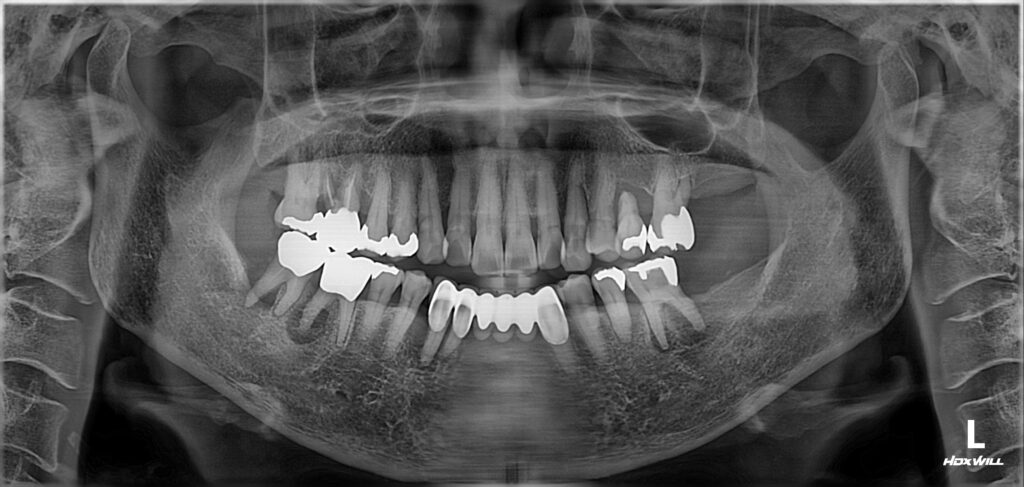

초진 상태

처음 오셨을 때의 구강 내 상태입니다.

대부분의 어금니가 심하게 흔들리고, 잇몸에서는 고름이 나오는 부위도 관찰됩니다.

이 정도까지 잇몸질환이 진행되었을 경우, 해당 치아를 더 이상 보존하는 것이 현실적으로 어렵습니다.

오히려 무리하게 살리려다 보면 주변 뼈를 더 잃게 되어 결국 임플란트마저 어렵게 되는 경우도 있습니다. 그래서 저희는 환자분께 발치 후 임플란트 치료로 계획을 세워드렸습니다.

발치를 하고 보니 역시나 뿌리까지 많이 오염되어있었습니다.

일정 수준 이상까지 치석이 진행되고 잇몸뼈가 파괴되면 치료가 어렵고, 억지로 치료한다고 하더라도 관리가 매우 어려워서 결국에는 빼게되는 상황에 이르게 됩니다.